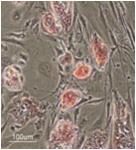

選取人腫瘤組織中的原發性腫瘤細胞進行培養該技術能夠鑑定來自患者的原發性腫瘤細胞的表征,因此可根據其主要細胞化學敏感性,惡性腫瘤,轉移酶活性和其它參數對患者的治療進行評估。在膠原或者3D凝膠中培養原發性腫瘤細胞,纖維細胞的過度生長可能對其產生抑制作用。而成纖維細胞在溫敏性水凝膠中不容易增殖,因此能選擇性增殖原代腫瘤細胞,以便後續進一步分析鑑別。

溫敏性水凝膠人結腸癌組織在溫敏性水凝膠中培養10天。只有原發性腫瘤細胞增殖。

圖 1:人體癌變結腸組織培養10天。

(提供者:Dr. S. Kubota, Dept. of General Surgery, St.Marianna University School of Medicine)

成纖維細胞在溫敏性水凝膠中生長受到抑制,而在膠原蛋白和其它許多3D凝膠培養基質中,長滿成纖維細胞,阻止癌細胞的增殖。